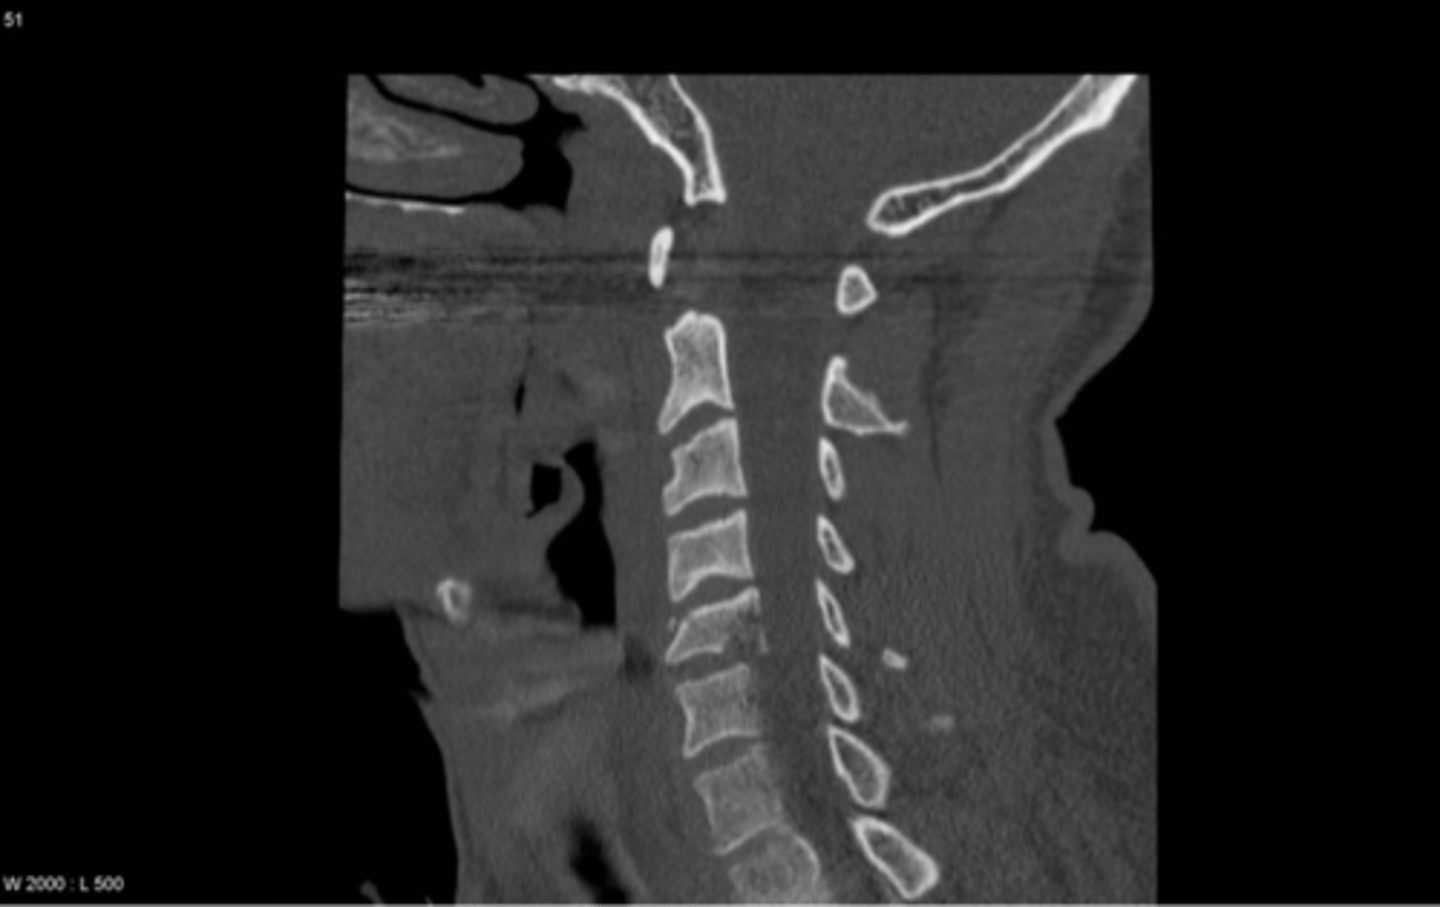

spinal compression fracture

cervical burst fracture